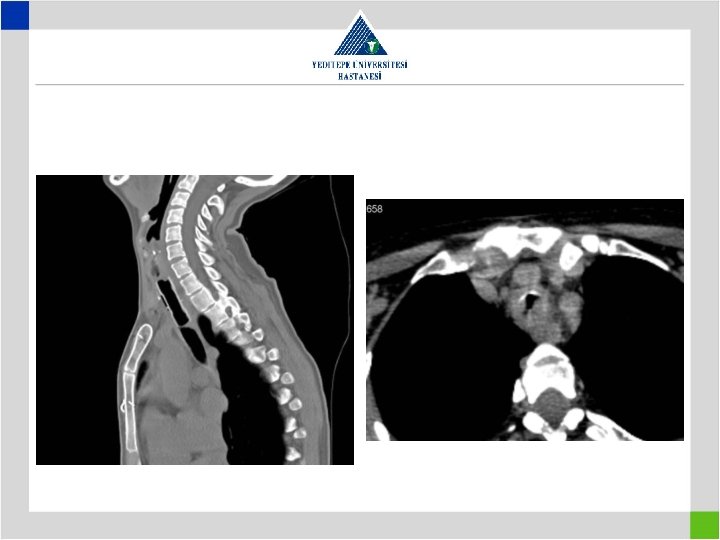

Diagnosis • Stenotic segment calculation to be correct • CT image in supine position may falsly indicate a preglottic stenosis – Overresection – increased anastomotic tension – restenosis • Pediatric trachea tolerates the tension poorly in comparison with adults – Insufficient resection – remaining fibrosis – restenosis